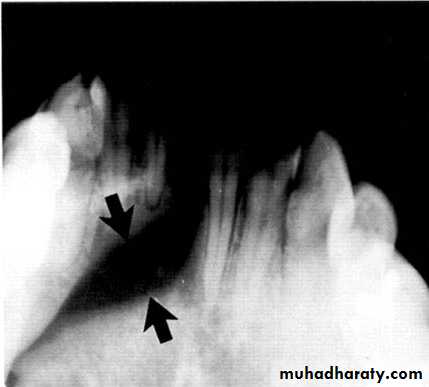

Central giant cell granuloma*A relatively uncommon, non- neoplastic mass in the jaws producing an expansile radiolucent soap bubble appearance.

*Age; <20 years. Female > Male.

*Teeth are vital, with some root resorption & migration of teeth. *History of trauma.

Multilocular appearance, expansion (arrowed) and considerable displacement of the adjacent teeth.

Buccal and lingual expansion (arrowed) and the undulating cortical border.